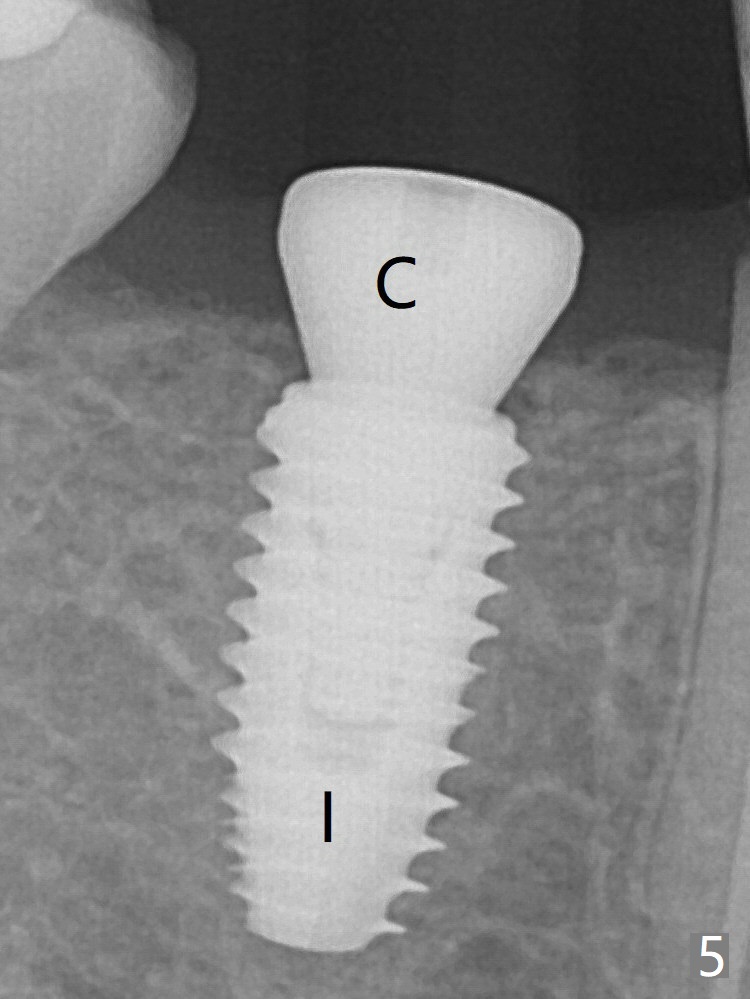

Everything happens so quick that when a 5.5x3 mm healing abutment is placed (Fig.4), you are pleased to feel that the implant is stable (Fig.5).  The patient returns for impression nearly 2 months postop (Fig.7,8).  It appears that the implant has osteointegrated without bone loss (Fig.7).  Guided surgery seems to be less traumatic than free hand one.  The soft tissue is healthy around the just placed cementation abutment (Fig.8 (5.2x4(2) mm).